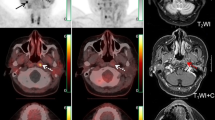

Among all participants involved, 23(50%) of them had osteoblastic bone lesions as major metastatic type, 13(28%) for osteolytic type and 10(22%) for mixed type. The diagnostic performance for different lesion types is summarized in Table 4, while the comparison of radiotracer uptake (SUVmax) in osteoblastic and osteolytic lesions is presented in Fig. 2. Representative imaging is shown in Fig. 3.

Images of a 69-year-old man diagnosed with prostate carcinoma who had a history of endocrine therapy for 2 years. (a) The maximum intensity projection (MIP) image of 18F-FDG showed moderate radiotracer uptake in a thoracic vertebra. (e) The maximum intensity projection (MIP) image of 68Ga-DOTA-IBA demonstrated more lesions in the cervical vertebra and pelvis. (b) An osteoblastic lesion in the C3 vertebra right attachment (curved arrows) was negative on 18F-FDG (SUVmax=2.0) and positive on 68Ga-DOTA-IBA (SUVmax=8.7). (c) Another osteoblastic lesion in the T10 vertebra left side (arrowheads) was both positive on 18F-FDG (SUVmax=5.2) and positive on 68Ga-DOTA-IBA (SUVmax=35.0). (d) Osteoblastic lesions in bilateral ilium (dotted arrows and arrows) were negative on 18F-FDG (left: SUVmax=1.4, right: SUVmax=1.6) and positive on 68Ga-DOTA-IBA (left: SUVmax=7.6, right: SUVmax=8.7). Follow-up imaging 3 months later confirmed the presence of these bone metastases. 68Ga-DOTA-IBA, gallium 68 (68Ga)-labeled DOTA-conjugate ibandronic acid; 18F-FDG, fluorine 18 (18F)-labeled fluorodeoxyglucose.